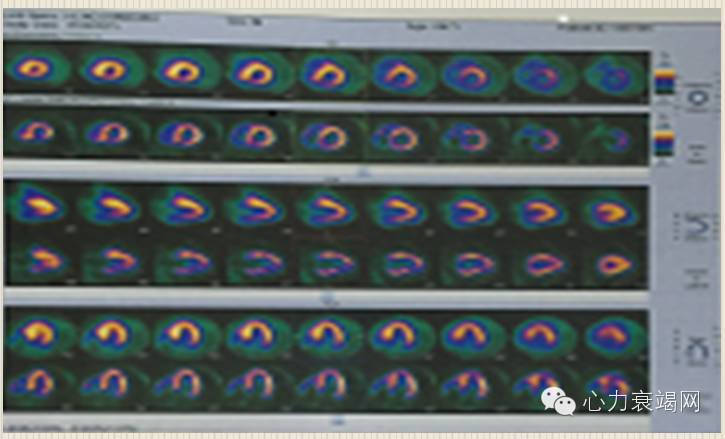

心肌活力评价:左室各节段血流灌注/代谢均大致正常,未见透壁性心肌梗死改变